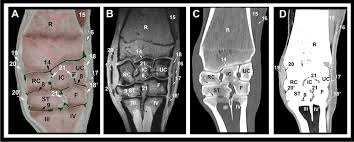

on a diagram

x-ray

on ct

mri